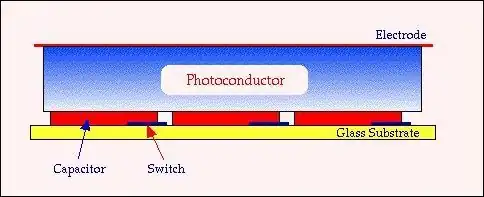

- Direct receptors are based on coupling a photoconductor to the active matrix array. Photoconductors such as amorphous selenium (a-Se) have been used, and the electric charge produced following X-ray interaction is detected by an array of pixels each consisting of an electrode and a capacitor – see the following figure:

- This charge is stored in each capacitor until it is read-out by the electronic switching circuitry. The photoconductor requires a voltage of the order of 5,000 V to be applied, using a surface electrode, so that the charge produced can be attracted to the pixel electrodes. Other photoconductors under investigation for this application include PbI2, PbO, TlBr and CdTe.